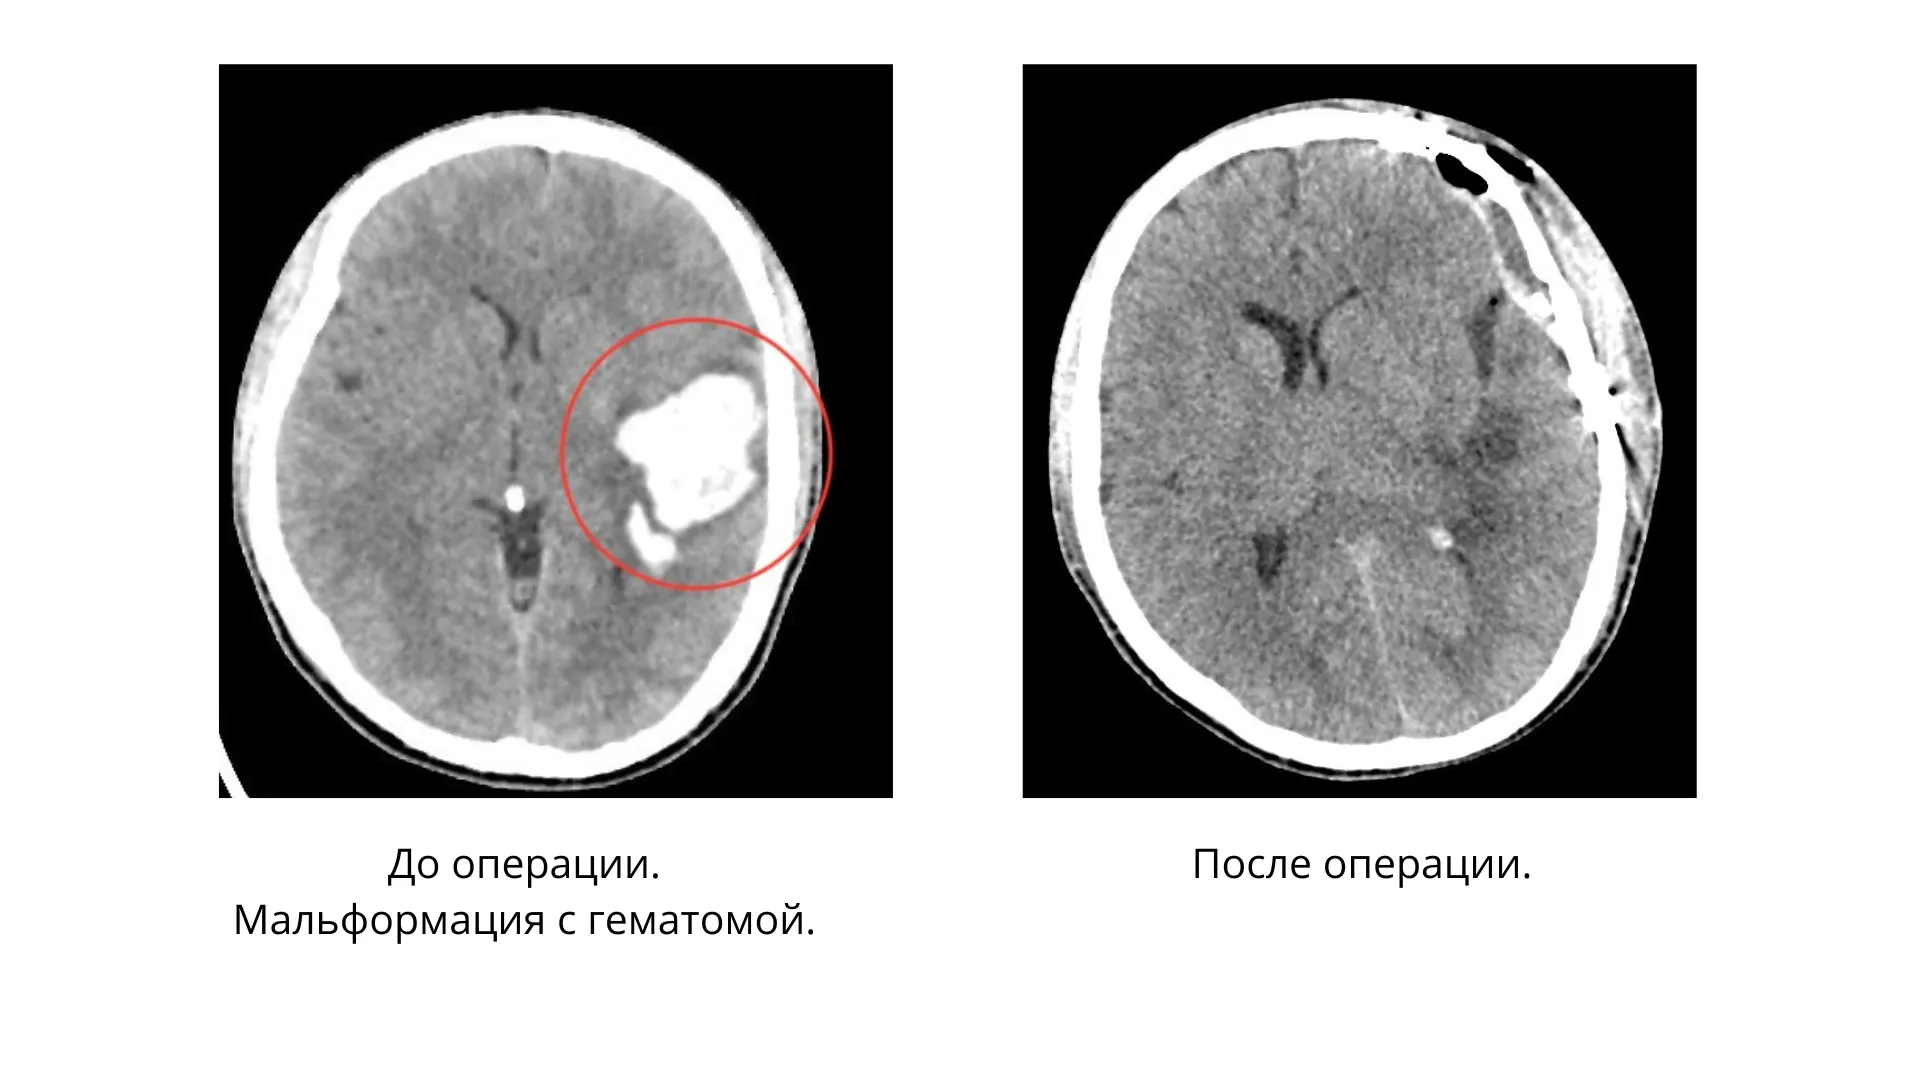

Заведующая отделением реанимации и интенсивной терапии МОНИКИ Наталия Бурда рассказала, что при проведении компьютерной томографии у пациента обнаружили внутримозговую гематому в левой височно-теменной области .Медлить было нельзя.

Нейрохирурги во главе с Ревазом Джинджихадзе провели костно-пластическую трепанацию черепа и удалили гематому с применением микрохирургической техники.

Операция прошла успешно. Пациент трое суток находился на лечении в отделении реанимации и интенсивной терапии № 2, а затем его перевели в отделение нейрохирургии. Сейчас молодой человек дома. У него прошли головные боли, нормализовалось давление и практически полностью восстановилась речь.